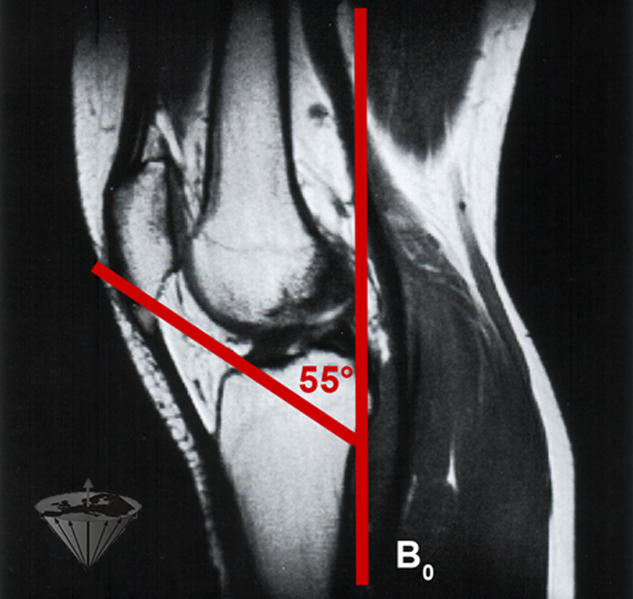

The magic angle is a precisely defined angle of approximately 54.7° (in most pub­­li­ca­tions rounded to 55°) to a strong exter­nal magnetic field at which two nuclei with a dipolar coupling vector have zero dipolar coupling. This phenomenon is applied in solid-state NMR spectroscopy as the magic angle spinning technique to re­move or re­duce dipolar couplings and thus increasing spectral resolution [⇒ Berendsen 1962].

When tendons in an MR imaging equip­ment are aligned at an angle of 54.7° re­la­­tive to B₀, the dipole coupling descends to zero. This was first reported in 1985 by Ful­ler­ton and col­lea­gues [⇒ Fullerton 1985]; they described an increase in T2 of the achil­les tendon from 0.6 to 22 ms.

Figura 17-19:

Black patellar tendon aligned — more or less — parallel to B₀ due to short T2/T2* with a bright lesion in the tendon just below the patella. This small bright area is not a magic angle effect (or “artifact”), but a chronic degeneration of the tendon (tendinosis).